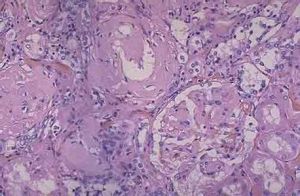

用剛果紅染色偏振光顯微鏡下觀察可見特異的蘋果綠色螢光)在血管壁及器官組織細胞外沉積為特徵鵻的健康搜尋一種進行性預後不良性疾病。澱粉樣物質可沉積於局部或全身主要累及心肝、腎、脾胃腸、肌肉及皮膚等組織。肝澱粉樣變性為全身性澱粉樣變性健康搜尋的一部分僅見於肝臟的澱粉樣變性目前尚未見報導。